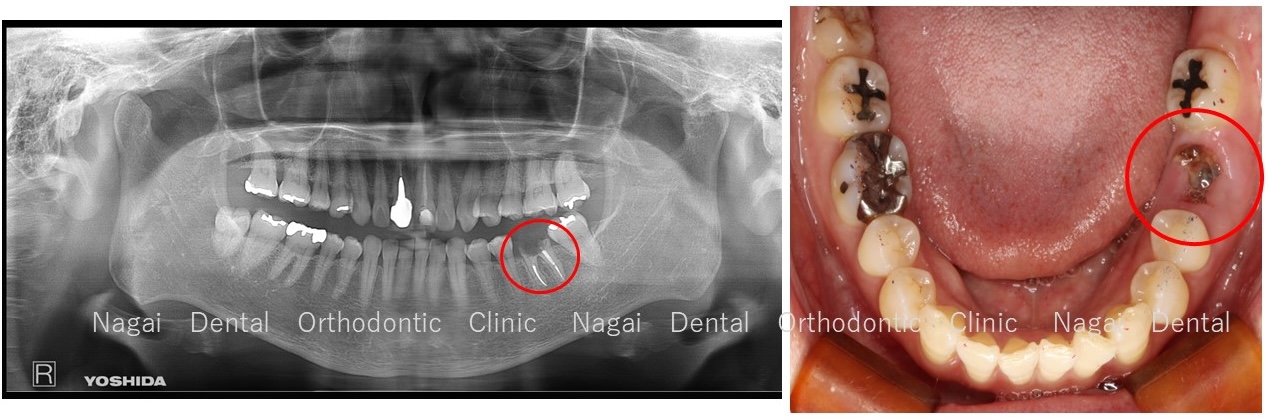

左下6番目の奥歯1本が最近、被せ物が外れてしまい、噛むと痛むとのこと。

数年前から、痛みが出たり、はぐきが腫れたりと、すっきりしない状態が続いていました。

調べると、歯を残すことが出来ない状況でした。

患者様とご相談の上、他の歯への負担がないインプラント治療を行うことにしました。